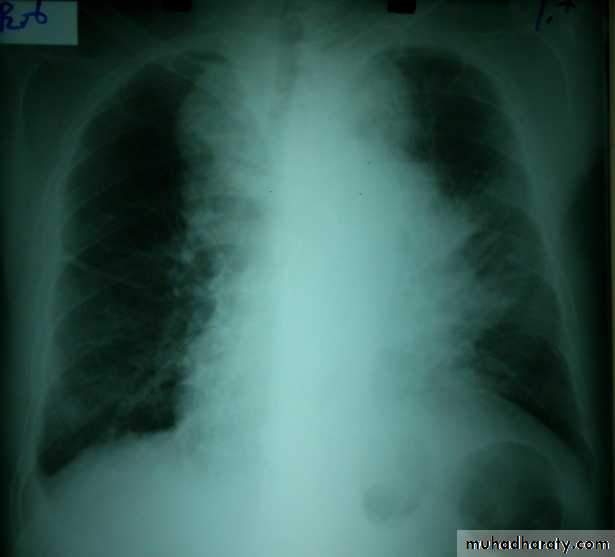

Secondary tumours of the lung:

Usually multiple and bilateral. No respiratory symptoms and the diagnosis is made by radiological examination. Breathlessness may occur if a considerable amount of lung tissue has been replaced by metastatic tumor. Usually from breast, renal, GIT, cervix, ovary or testicle or lymphangitic carcinomatosis.

Chest radiography shows multiple pulmonary nodules of varying sizes consistent with metastatic cancer.

Chest CT scan shows multiple round nodules and masses of varying sizes in both lungs, consistent with metastases. There are also small bilateral pleural effusions.

Multiple and bilateral secondaries